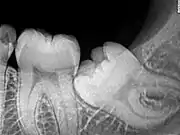

Impacted 2nd molar (red arrow) with developing wisdom tooth (green arrow)

There is no standard to screen for wisdom teeth. It has been suggested, absent evidence to support routinely retaining or removing wisdom teeth, that evaluation with panoramic radiograph, starting between the ages of 16 and 25 be completed every 3 years. Once there is the possibility of the teeth developing disease, then a discussion about the operative risks versus long-term risk of retention with an oral and maxillofacial surgeon or other clinician trained to evaluate wisdom teeth is recommended. These recommendations are based on expert opinion level evidence.[19] Screening at a younger age may be required if the second molars (the "12-year molars") fail to erupt as ectopic positioning of the wisdom teeth can prevent their eruption. Radiographs can be avoided if the majority of the tooth is visible in the mouth.